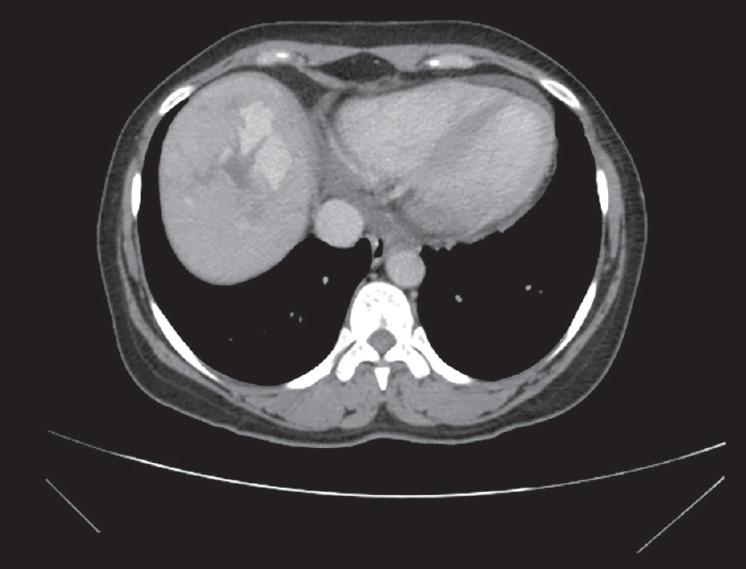

A 44-year-old woman came with complaints of recurrent episodes of hematemesis and epistaxis. Patient had a family history of similar complaints. Patient underwent esophagogastroduodenoscopy (EGD), which revealed telangiectasia in the stomach. Imaging of the abdomen showed features suggestive of arteriovenous shunting.

一名44岁女性因反复呕血和鼻出血前来就诊。患者有类似症状的家族史。患者接受了食管胃十二指肠镜检查(EGD),结果显示胃部有毛细血管扩张。腹部影像学检查显示有动静脉分流的特征。